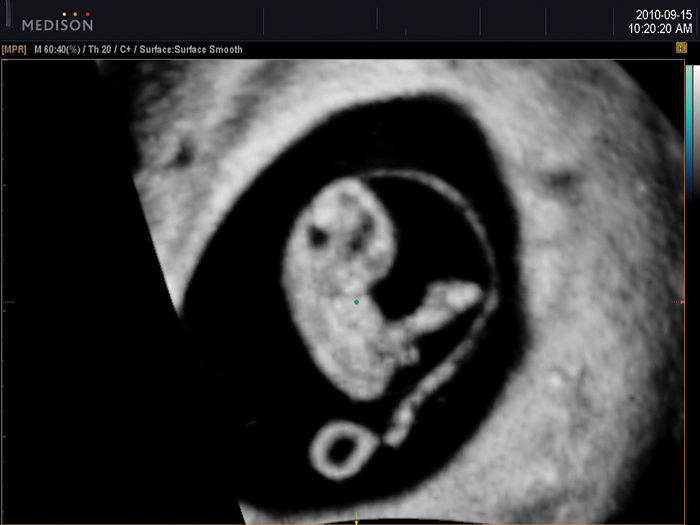

8 hetes magzat képe a coronalis síkban 2D módban8 hetes magzat képe coronalis síkban HD Volume Imaging módban

HDVI™ is based on non stationary adaptive filtering resulting in removal of unwanted speckle and noise whilst increasing visualization of edges and small structures in volume data. HDVI™ uses a 3D processing algorithm that is based on 3D matrix processing of volume data.

The essential feature of this 3D processing algorithm is matrix image processing which allows more accurate rendered information calculated from the voxel data of the acquired volume data.

By using this calculation method, a clear and improved image is shown in the rendered and multi-planar views.

HD Volume Imaging™ (HDVI™) removes artifacts and incorporates a speckle reduction filter without compromising details but at the same time emphasizing the edge and structures. Therefore, 3D rendered image and multi-planar view provides an image quality with improved contrast and resolution. According to the result, it shows that the speckle noise of the image with HDVI™ is lower while the edge enhancement are higher, compared to the Original.